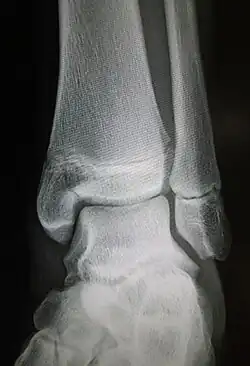

Maisonneuve fracture

| Radiograph showing a Maisonneuve fracture of the proximal fibula | |

The Maisonneuve fracture is a spiral fracture of the proximal third of the fibula associated with a tear of the distal tibiofibular syndesmosis and the interosseous membrane. There is an associated fracture of the medial malleolus or rupture of the deep deltoid ligament of the ankle. This type of injury can be difficult to detect.[1][2]